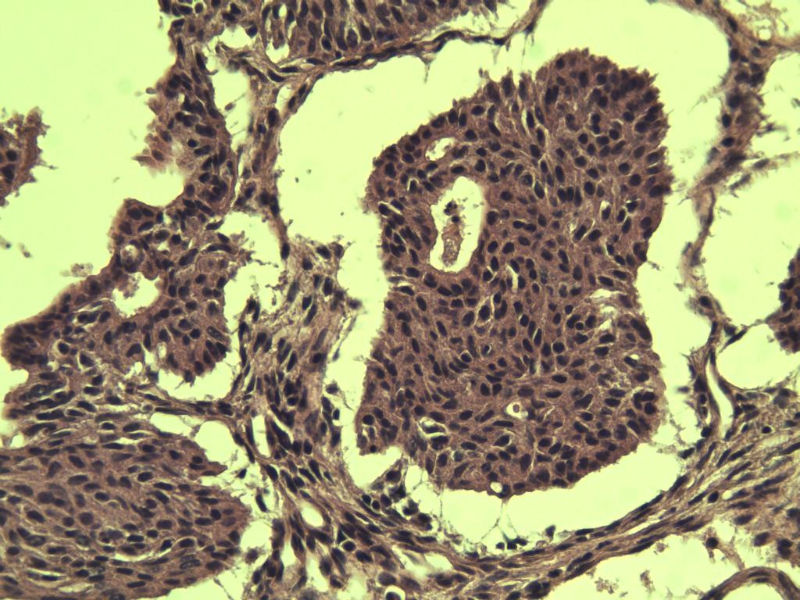

这是另外一个 40岁 经期延长 流血量增多 半年 这是蜕膜样变吧 有什么意义吗? 要报告不?